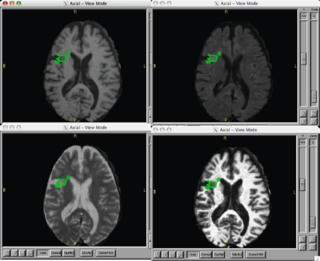

Our goal is to automatically, or with little or no manual human rater input, accurately tissue classify our example lupus data-set into gray, white, csf, and lesion classes.

Using an exemplar case that has already been processed using non-NAMIC kit tools:

- Use existing NA-MIC kit to coregister T1, T2, Flair

- Use the EM Segment in slicer 2-3.X to classify grey, white, csf, and white matter lesion

- Summarize the volume and location of lesions